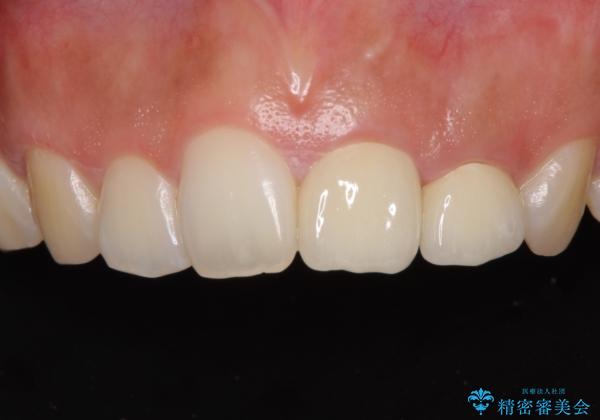

仮歯装着の時点で自然な見た目となり、オールセラミッククラウンを装着した際には、まるで自分の歯のようと喜んでくださいました。

長年変色を気にしており、もっと早くに治療を行えば良かったとおっしゃっていました。